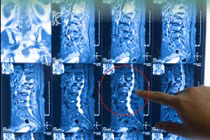

Hình ảnh phim chụp đốt sống của bệnh nhân trước và sau 3 tháng tái khám - Ảnh BVCC

Hình ảnh X-quang và MRI cho thấy: Xẹp đốt sống tiến triển nặng trên 50%; Mảnh xương chèn ép ống sống; Tổn thương tuỷ sống ngang mức... Bệnh nhân buộc phải phẫu thuật để giải ép thần kinh và cố định cột sống.